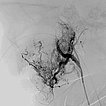

Digital subtraction angiography (DSA) after injection into the right common carotid artery shows the infantile hemangioma mainly supplied from the external carotid artery, as expected.

Digital subtraction angiography (DSA): After insertion of a 4F diagnostic catheter transarterially into the external carotid artery, selective advancement of a microcatheter into the maxillary artery. The infantile hemangioma presents as typical contrast pooling (“tumor blush”). The transvenously inserted balloon blocks the venous outflow and is clearly visible. Embolization was then carried out with particles of 150 micron size and without unintended venous outflow.